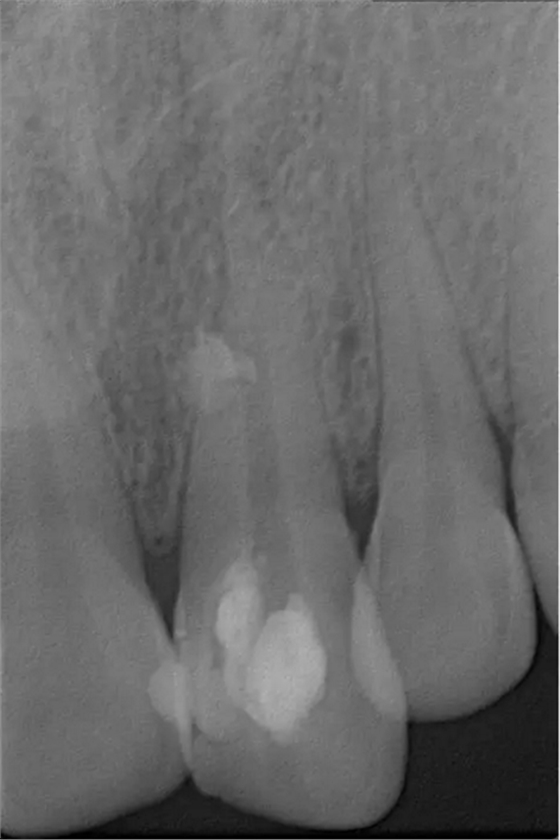

術(shù)前診斷片